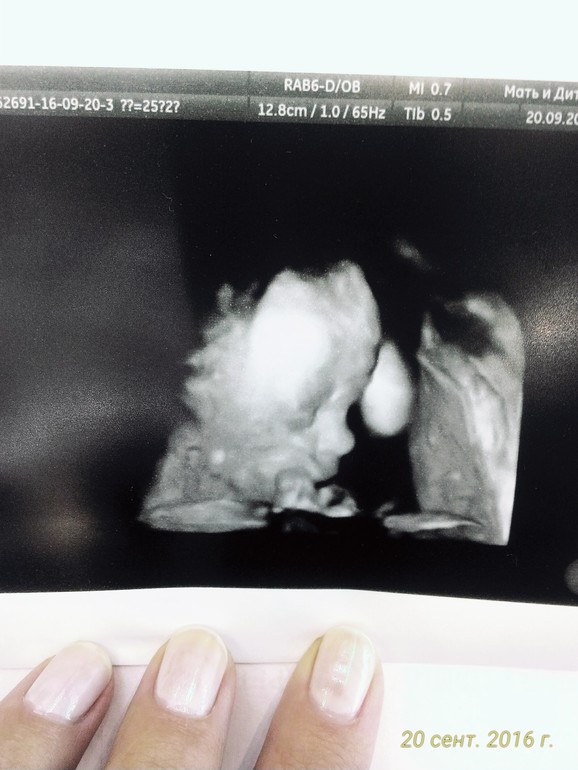

А 20 сентября, на сроке 25+2 мы пошли на 4 D узи!)))) Но эта фотка, собственно все))))) из 3-4 D))) Еще немного увидели нашу сладость в 3D эффектах... Это нечто!!!!! Но,мы растим шпиона))) Эта фотка, и те секунд 10 видео, мы успели лицезреть, пока деточка не проснулась и не поняла, что его снимают))) Отворачивался, вертелся.... Меня еже крутили как порося на вертеле...как ни повернут, и этот хитрый жук попой)))) Даже вагинальным датчиком смотрели, темечко подсосвывает и все!))) Она уже через живот поворачивает мордашку к датчику...он поворачивается...и тут же рукой закрывает))) Муж уже ржал, говорит-правильно сын не сдавайся, уж если решил-никакой съемки-так тому и быть!))) Я уже уговаривала, мол сыночек, не нужно скромничать-тут не такой принцип, что меньше показал, меньше заплатили)))) Мама с папой оплатят по полной.... и сладенькое ела...))) никак...Решили не мучать ни меня ни сыночка, и прийти на 30-32 недельке еще раз попробовать)))

Все у нас хорошо! Вот наши 834 грамма счастья, подпирают щечку кулочком!!!!